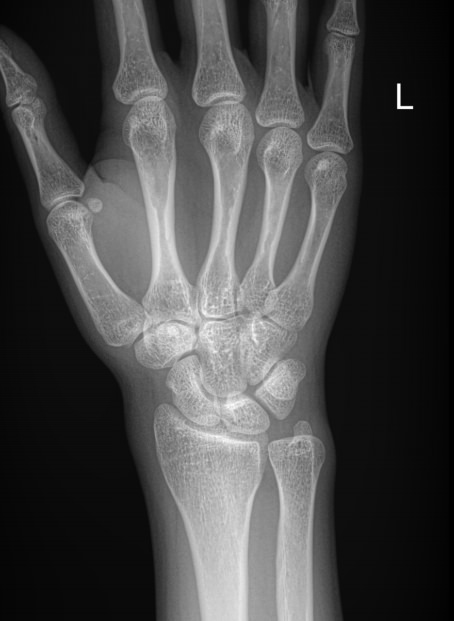

Для диагностики патологии суставов обычно достаточно рентгеновского снимка ― на нем отлично будут видны все особенности болезни, а также ее стадия. Чтобы выбрать правильную тактику лечения, необходимо определить, на каком этапе развития заболевания пациент обратился за помощью.

Что показывает рентген пястно-запястных суставов

На снимке могут быть видны следующие патологии:

• Сужение или расширение суставной щели, обызвествления, выросты или выпот в ней;

• Несовпадение элементов сустава друг другу из-за вывиха;

• Изменения в костной ткани и надкостнице ― в результате ее разрежения, уплотнения или воспаления;

• Утолщение мягких тканей;

• Реже встречаются переломы и опухоли.